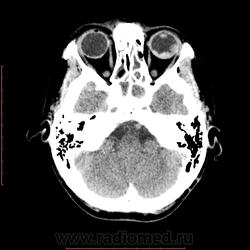

КТ орбит. Образование левого глазного яблока

Женщина 57 лет обратилась с жалобами на снижение зрения левого глаза. На УЗИ объемное образование левого глаза. Написал DDs меланома, ретинобластома.

Меланома - да, надо исключать. (наиболеее вероятно).

Рентинобластома - крайне маловероятна (после 5-ти лет эта опухоль практически не встречается).

Я тоже склоняюсь больше в сторону меланомы. Ретинобластома врожденная опухоль, в 90% случаев диагностируется как вы и сказали до 5 лет, у взрослых встречается редко и в 95% содержит обызвествления, но в дифф.ряд указал на всякий случай.